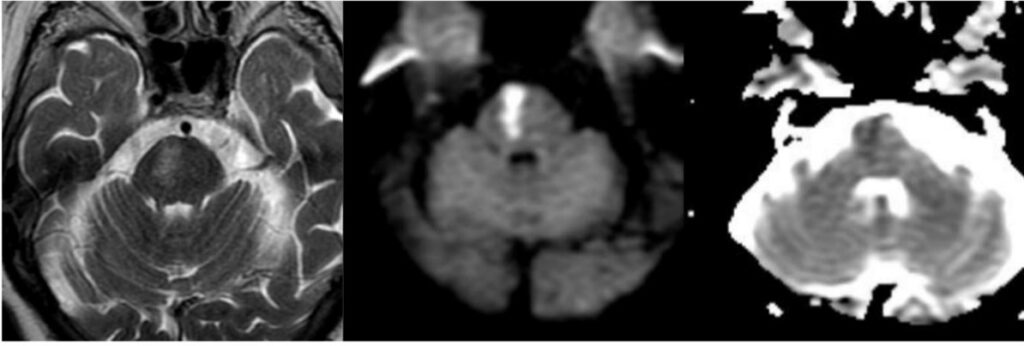

El presente caso ilustra un infarto isquémico del mesencéfalo medial, con una distribución paramediana bilateral y predominio a nivel del tegmento, acompañado de extensión caudal limitada hacia la unión pontomesencefálica. Este patrón topográfico, identificado mediante la combinación de secuencias de difusión y mapas ADC, es característico de la afectación de las ramas perforantes paramedianas del segmento distal de la arteria basilar y/o del segmento proximal de la arteria cerebral posterior, responsables de la irrigación del mesencéfalo medial, y ha sido descrito en infartos mesencefálicos mediales bilaterales dependientes de estas ramas perforantes.(5, 16)

En términos topográficos, la bilateralidad y simetría de la lesión constituyen un elemento clave para su correcta interpretación. A diferencia de los síndromes mesencefálicos alternos clásicos, como los síndromes de Weber o Benedikt, en los que el compromiso es típicamente unilateral y se extiende hacia los pedúnculos cerebrales, en este caso la lesión se encuentra confinada al tegmento medial, sin afectación significativa de las estructuras laterales, patrón previamente reportado en series imagenológicas de infartos mesencefálicos mediales.(5, 16) Este hallazgo permite descartar un patrón peduncular y refuerza el diagnóstico de un infarto mesencefálico medial.

La extensión rostro-caudal observada, con compromiso adicional del puente rostral, no debe interpretarse como la coexistencia de lesiones independientes, sino como la expresión de un territorio vascular continuo, fenómeno descrito en infartos dependientes de perforantes paramedianas largas.(17, 18) En este contexto, el análisis del eje rostro-caudal resulta tan relevante como la evaluación dorsoventral, en especial en lesiones localizadas en zonas de transición anatómica.

En este caso, la lesión se localiza predominantemente a nivel del mesencéfalo medial, con una distribución paramediana bilateral y extensión caudal limitada hacia la unión pontomesencefálica. Este patrón topográfico permite integrar los hallazgos imagenológicos dentro de un infarto mesencefálico medial y diferenciarlos de otros síndromes mesencefálicos clásicos con compromiso lateral o peduncular.(5)